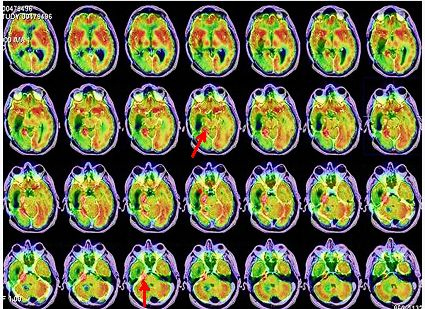

Nuevamente, en el seguimiento se detecta aumento de CEA (32,4 ng/ml), siendo el CT toráco-abdómino-pélvico normal. La RNM cerebral mostró una recidiva tumoral de 15 x 17 mm en lóbulo temporal derecho profundo (cuerpo-cola del hipocampo), junto al área de resección temporal previa. Se realiza estudio FDG PET-RNM cerebral (procedimientos separados con fusión posterior) que confirma la recidiva tumoral temporal derecha profunda (fig. 1).